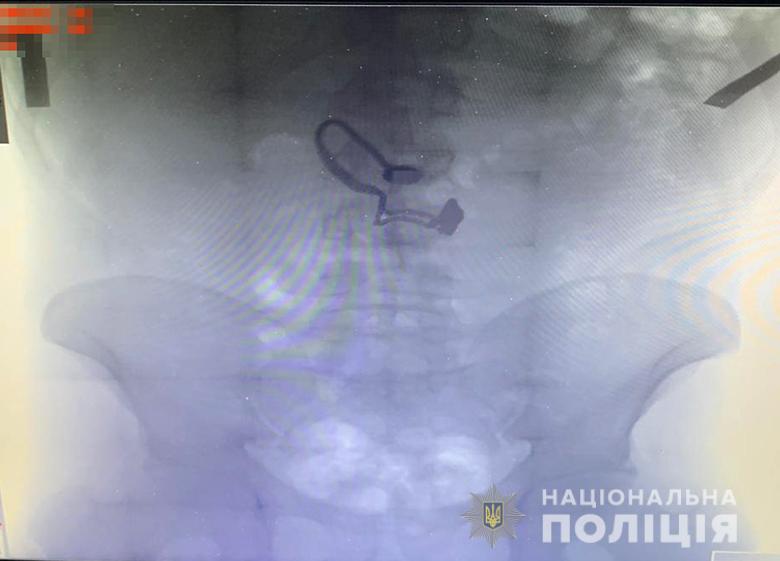

Грабителем оказался 26-летний житель Луганской области, ранее уже судимый за кражи. Его задержали. Во время поверхностного осмотра у мужчины нашли кошелек потерпевшей. Позже он признался полицейским, что сорванную цепочку проглотил.

"Во время медосмотра на рентген-снимке задержанного врачи обнаружили украшение", - сообщают в полиции.